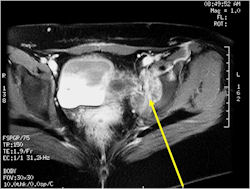

- Pelvis

Radiographic Presentation

- Soft Tissue Mass in 90% of of cases

- Ewing sarcoma responds well to chemotherapy. Often there is a dramatic reduction in size of the tumor.

- Pelvic Ewing sarcoma have a worse prognosis than other areas